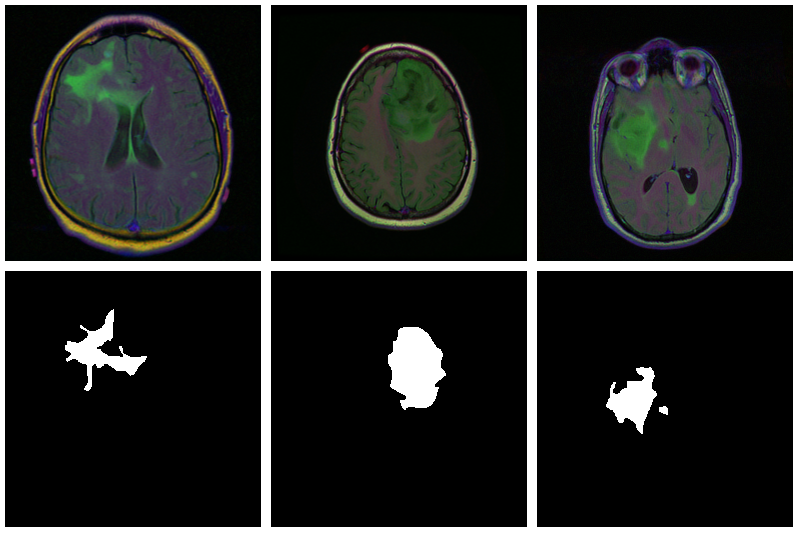

With U-Net, domain applicability is as broad as the architecture is flexible. Here, we want to detect abnormalities in brain scans. The dataset, used in Buda et al. (2019), contains MRI images together with manually created FLAIR abnormality segmentation masks. It is available on Kaggle .

Here are three examples where the masks do indicate abnormalities:

Let’s see if we can build a U-Net that generates such masks for us.